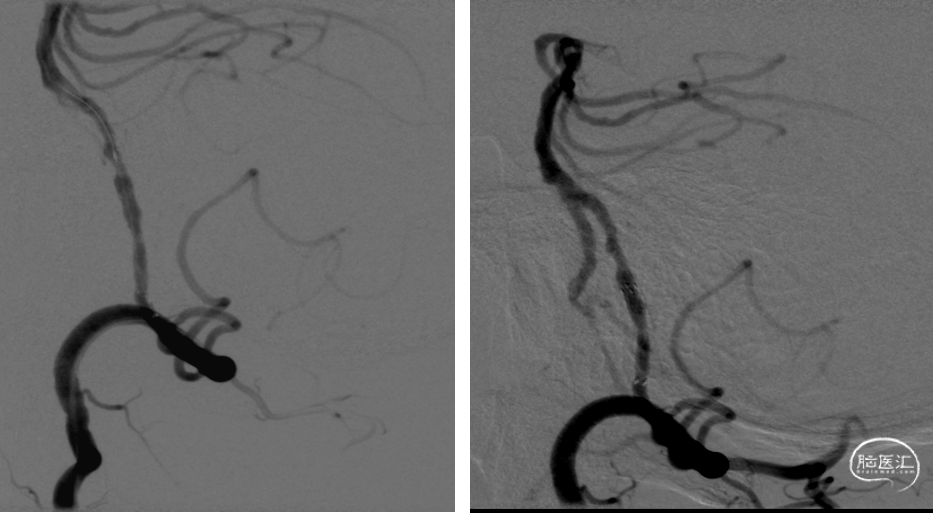

DSA提示:双侧颈内动脉及颅内血管未见明显狭窄,右侧椎动脉优势,左侧椎动脉纤细,V4段闭塞。右侧椎动脉起始处重度狭窄,右椎V4段及基底动脉近端局限性重度狭窄。患者反复间断发作头晕,考虑后循环缺血引起的TIA发作,且强化药物治疗效果不佳,有介入治疗适应症。

脑血管造影:主动脉弓+右侧颈总动脉造影。

左侧颈总动脉造影。

左侧锁骨下动脉造影。

右侧锁骨下动脉造影。